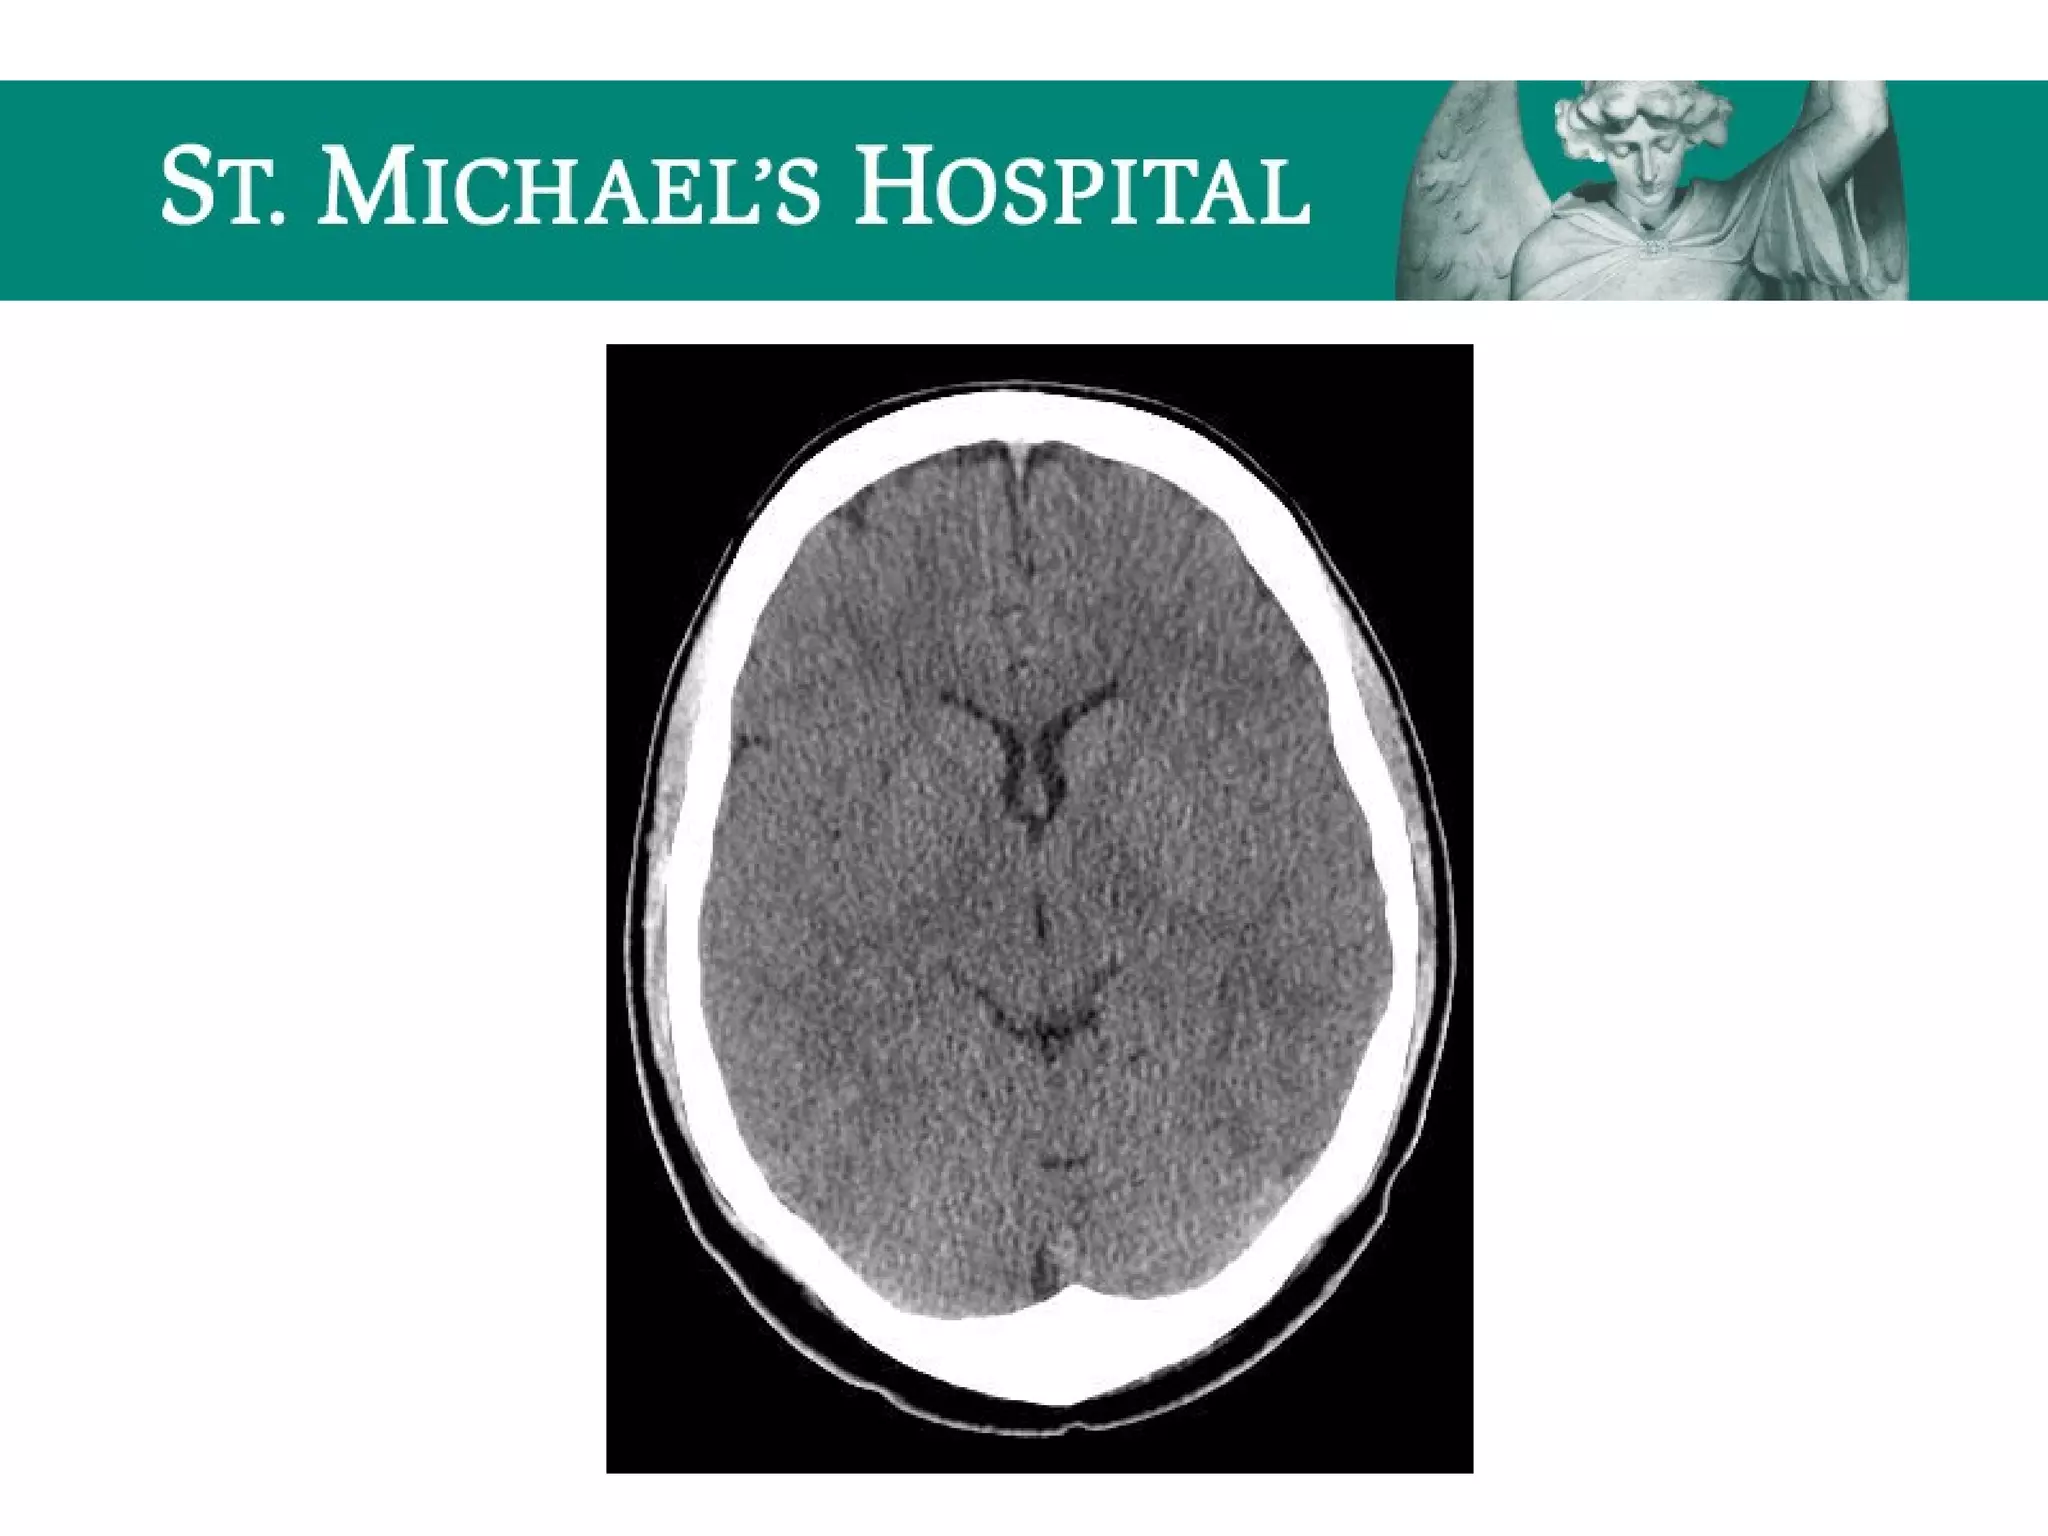

Communicating Hydrocephalus

 Blockage of CSF flow over the cerebral convexities/absorption at the arachnoid

granulations secondary to:

– SAH, meningeal mets, granulomatous meningitis

 Rapid CSF production

 eg. choroid plexus papilloma

 Radiological features:

 Symmetrical enlargement of the lateral, third and fourth ventricles

 Normal/effaced cerebral sulci

 Dilatation of subarachnoid cisterns

 Periventricular low attenuation  transependymal flow of CSF